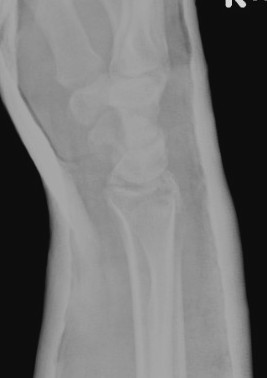

Dorsal radiocarpal dislocation with dorsal rim fracture

Dorsal radiocarpal dislocation with radial styloid fracture